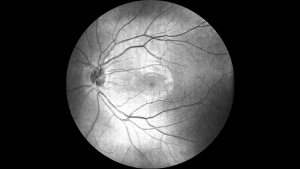

• Зображення сітківки в режимі реального часу під кутом 45° SLO

Mocean® 3000 одночасно отримує ОКТ-зображення і зображення очного дна під кутом 47 градусів на основі скануючого лазерного офтальмоскопа (SLO), забезпечуючи огляд сітківки в режимі реального часу, що дозволяє легко локалізувати ділянку ураження ще до отримання зображення.

Зображення очного дна

МетодЛінійна скануюча лазерна офтальмоскопія (LSLO)

Мінімальний діаметр зіниці 3,0 мм

Поле зору 45 ± 1°